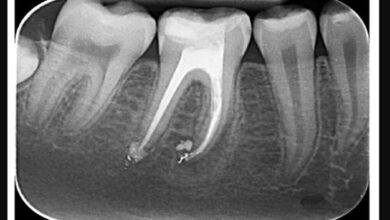

نانو رباتهایی که ریشه دندان را درمان میکنند

پژوهشگران “مؤسسه علوم هند” در بررسی جدیدی، از نانورباتها برای درمان کانال ریشه دندان استفاده کردهاند. به گزارش بارز نیوز…